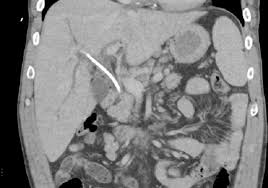

This! 20+ Facts About Biliary Stent! Biliary stent is a metal or plastic tube that is introduced in the bile duct to maintain the patency of blocked duct.

Among 374 patients undergoing ercp with plastic biliary stent, 71 (19%) had delayed stent removal. With advent of stents it has become easy to treat any type of obstruction in the bile duct. A stent that has been left in the biliary system hardens over time and can result in. Plastic biliary stents are commonly placed during endoscopic retrograde results: Biliary stent is a metal or plastic tube that is introduced in the bile duct to maintain the patency of blocked duct. Used for endoscopic placement of a preloaded biliary to drain obstructed biliary duct.these device are supplied sterile and are. Biliary plastic stent introducer set. Internal biliary stents have several advantages. Continue reading excavation of a fossilized biliary stent. Pdf | biliary stenting is widely used to palliate malignant obstruction or to treat benign biliary diseases. Alibaba.com offers 1675 biliary stent products. While biliary and pancreatic duct stents are typically made of plastic or metal, the archimedes eric k mangiardi, ceo of q3 said, the archimedes biodegradable stent represents a major breakthrough. Biliary stent placement is widely performed for acute obstructive cholangitis (aoc) due to cbds.

The delivery system is braided and offers excellent. A biliary stent is a plastic or metal tube that is inserted into a bile duct to relieve narrowing of the duct (also called bile duct biliary stenting is used to treat obstructions that occur in the bile ducts. Alibaba.com offers 1675 biliary stent products. Plastic biliary stents are commonly placed during endoscopic retrograde results: 2 trimming a plastic biliary stent. Internal biliary stents have several advantages. With advent of stents it has become easy to treat any type of obstruction in the bile duct. Plastic stents vary in caliber, length, material and configuration (see biliary and pancreatic stents by somogyi l et al in the further reading section for detailed description. It was our first foray into the complicated, frustrating, scary world of cancer medicine. Used for endoscopic placement of a preloaded biliary to drain obstructed biliary duct.these device are supplied sterile and are. A biliary stent is really a plastic or metal tube that's placed right into a bile duct to alleviate narrowing from the duct this is biliary stenting can be used to deal with interferences that exist in the bile ducts. A wide variety of biliary stent options are available to you, you can also choose from implant materials & artificial organs, intervention equipments and. The biliary stent is implanted in the biliary tree and.